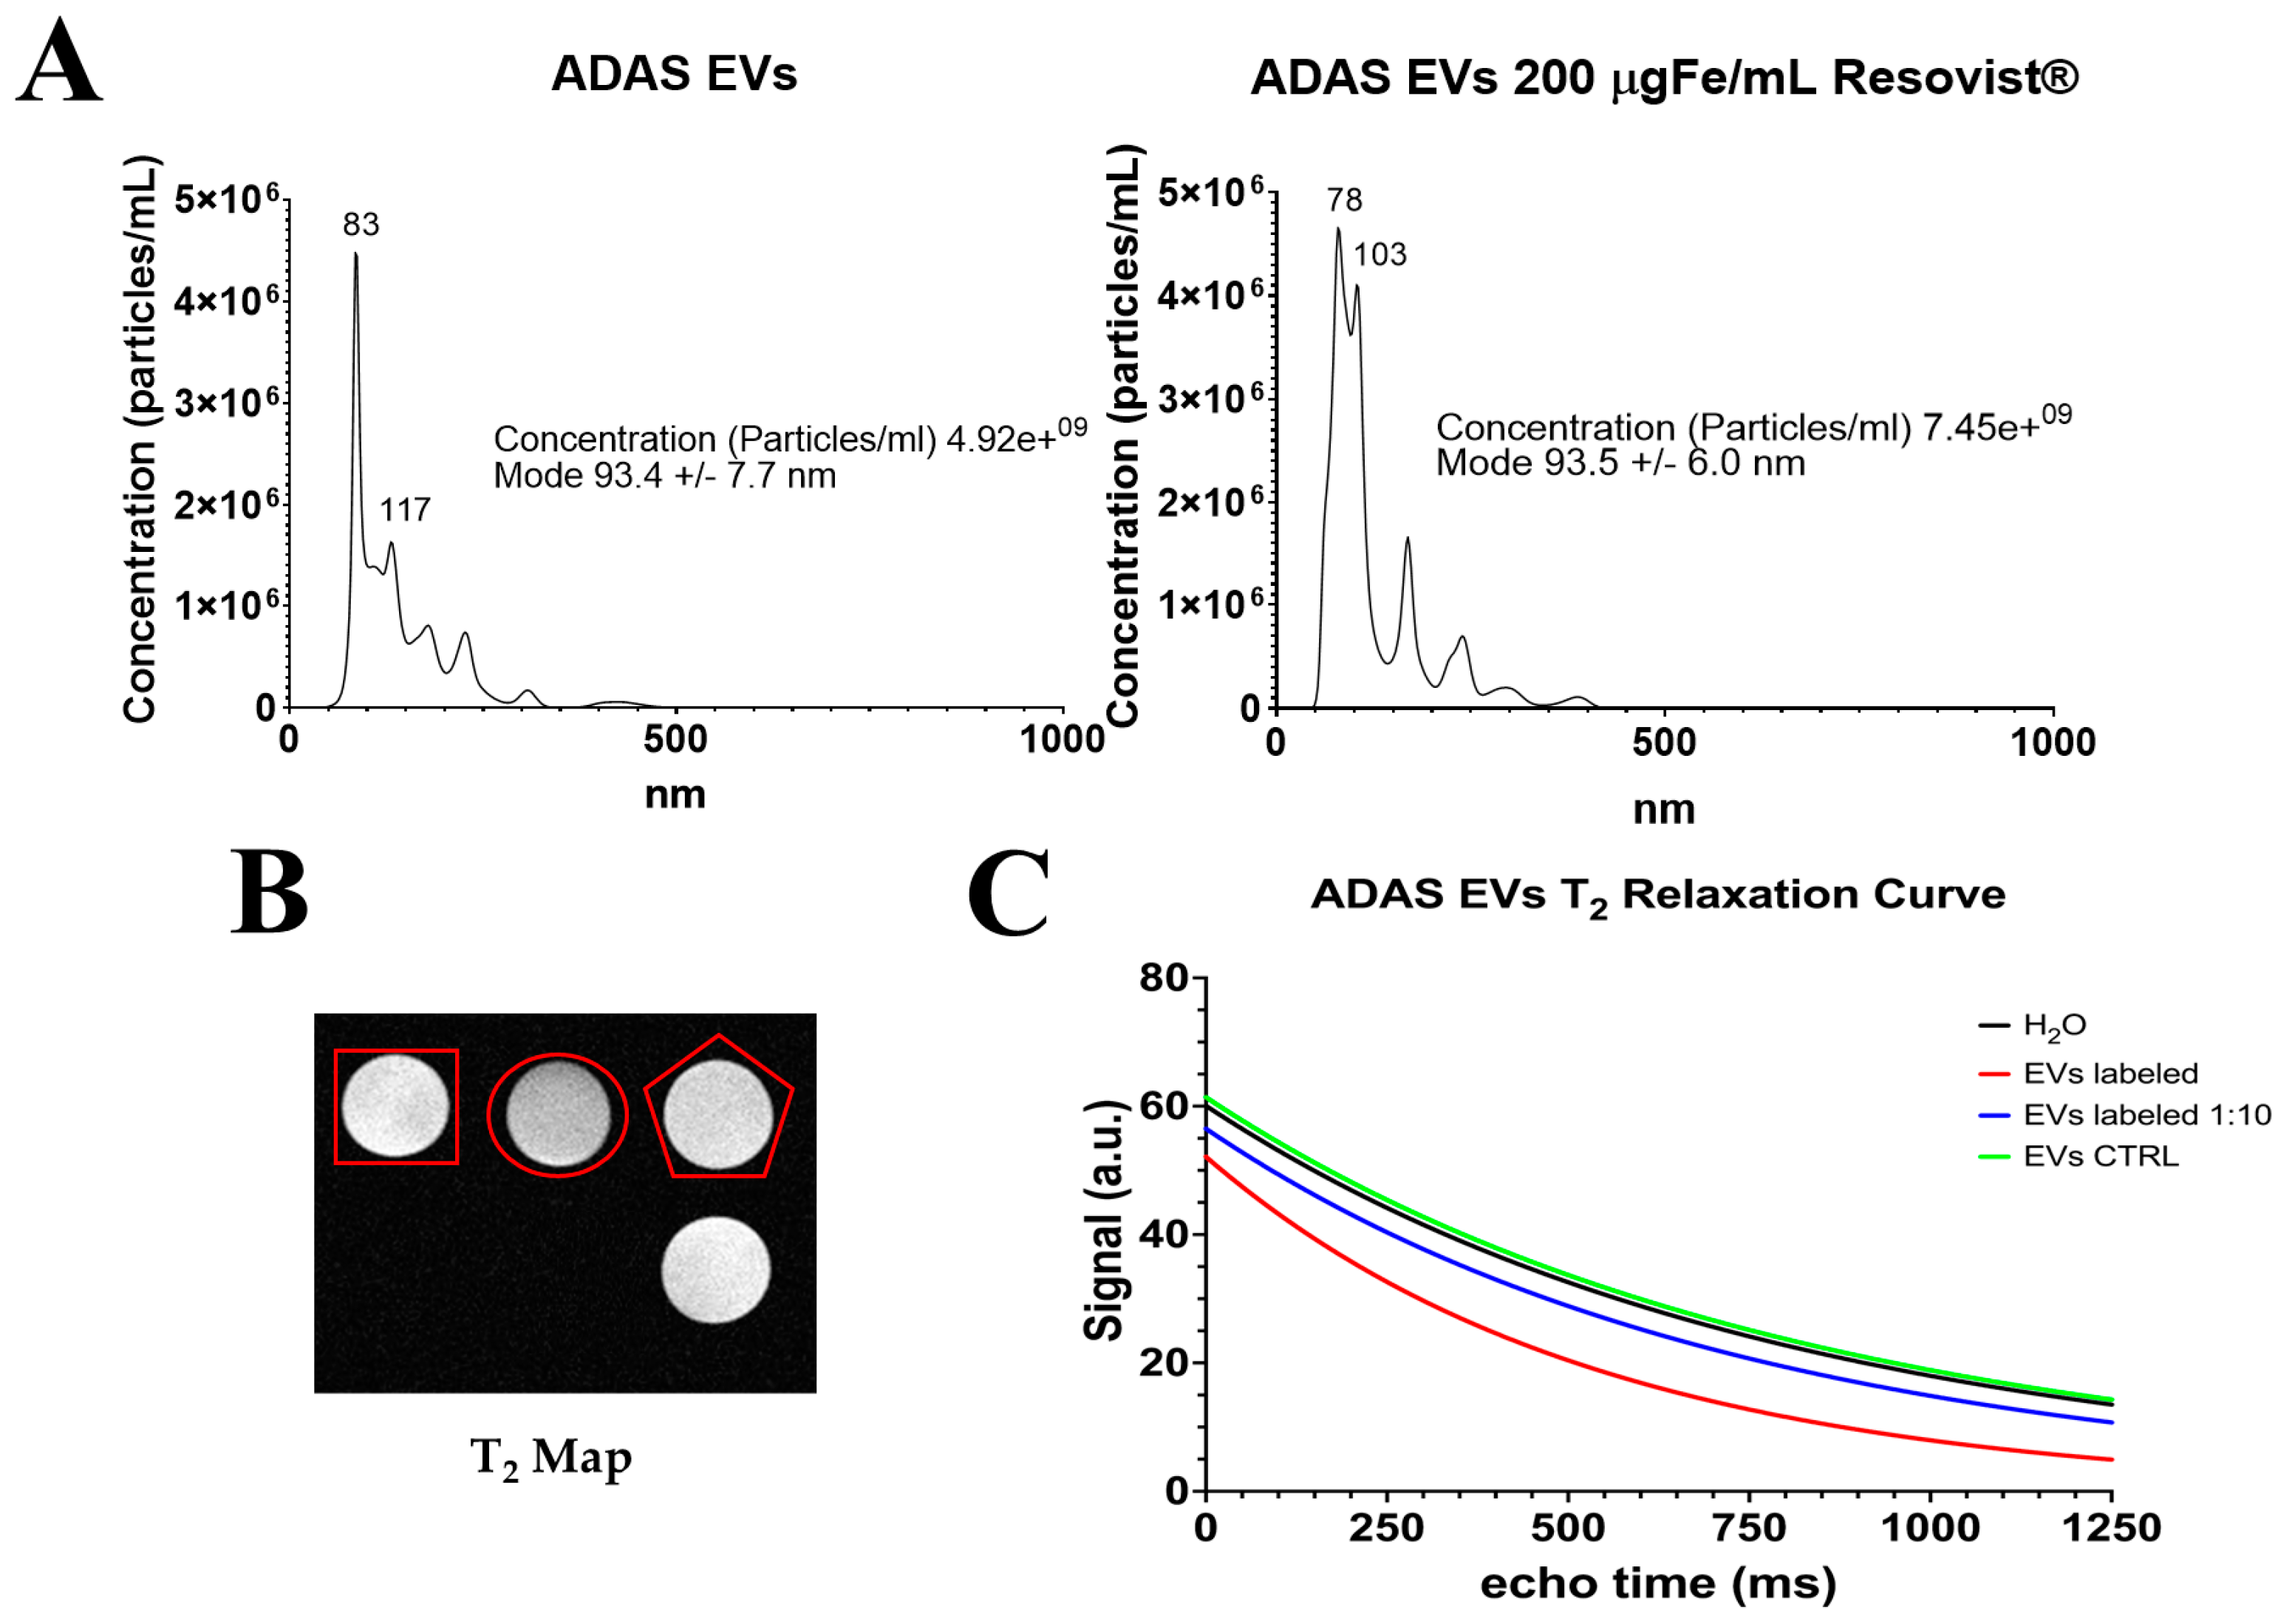

2.4. Extraction of Extracellular Vesicles from ADAS-Labeled Cells